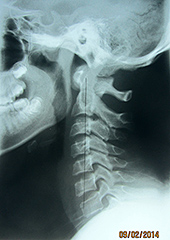

Fig. 1: A-P Open Mouth

In Figure 1, we can see significant imbalances. Many of these imbalances originate from the imbalances found in the feet and can be seen on the digital foot scan (Figure 2). Remember, the body is a compensatory mechanism and any disturbance between atlas, axis and the occiput are typically a compensation for the imbalances below. Therefore, for maximum biomechanical potential, you must address the feet imbalances first.

In Figure 1, we can see there is rotation of the axis, however, the right pillar of the atlas is wider than the left pillar of the atlas because the atlas, too, is rotated and the right pillar is closer to the tube. Finally, if you notice the open mouth, it too, is angled to the left, showing abnormal rotation in the occiput, atlas and axis.